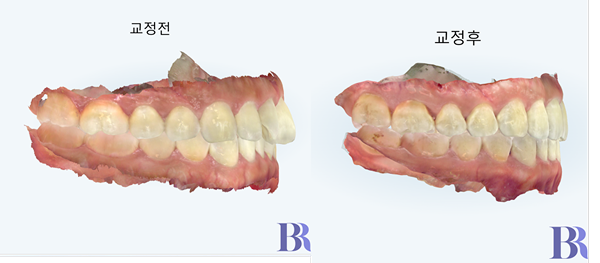

인비절라인 치료평가의

또 하나 중요한 포인트

'어금니 교합'

또 하나 인비절라인 치료에서

중요하게 봐야 할 것은 바로

어금니 교합인데요.

어금니 교합이 이전보다

훨씬 더 긴밀해졌습니다.

윗니와 아랫니를 톱니바퀴처럼

교차하게 만들었습니다.